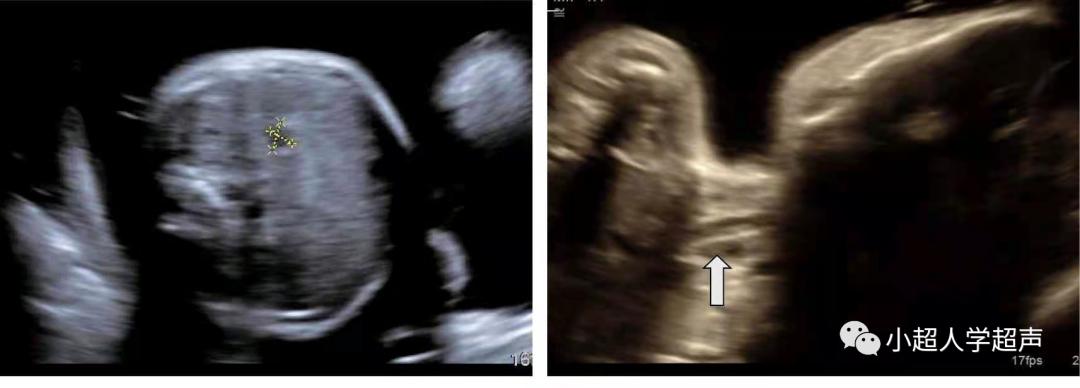

直接征象 :食道盲端的囊袋征,胎儿颈部的囊性结构

产前超声很难显示食管闭锁部位,所以很难进行准确的分型,常常通过羊水过多、胃泡不显示、腹围小等一些间接征象并动态观察胎儿吞咽羊水时是否出现颈部的“囊袋样”无回声来提示食管闭锁,因此产前超声对食管闭锁的检出率各家报道不一,大多不超过50%。

食管闭锁的“囊袋样”无回声在检查过程中会观察到无回声结构 随胎儿吞咽动作大小有所改变 。